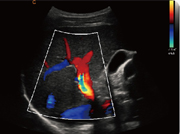

门静脉,彩色模式